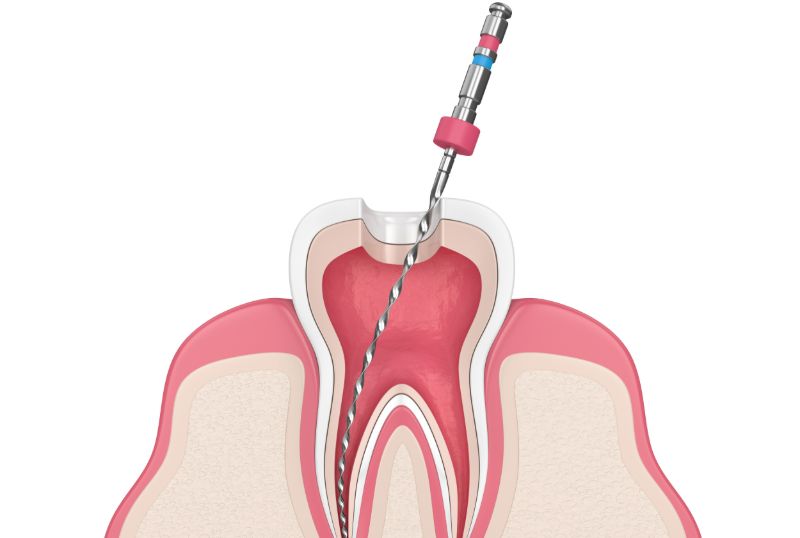

歯の根にある歯髄(しずい:神経や血管など)が通っている管を根管といいます。

根管治療は、この歯髄が炎症や感染を起こしたときに行われる治療です。

深いむし歯や歯の亀裂、外傷などが主な原因になります。

炎症や感染を放置すると、 歯の痛みや歯肉が腫れたり、根の周囲に炎症が広がったりします。

リンパ節が腫れ、全身に影響を及ぼすこともあります。

根管治療により、これらの症状の軽減や治癒を図ります。